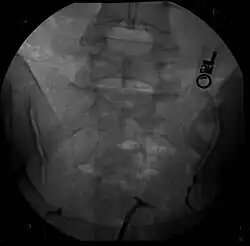

Hysterosalpingography of a T-shaped uterus.

Women are often diagnosed with this condition after several failed pregnancies, proceeded by exploratory diagnostic procedures, such as magnetic resonance, sonography, and particularly hysterosalpingography.[6][7][8] In such studies, a widening of the interstitial and isthmus of uterine tube is observed, as well as constrictions or narrowing of the uterus as a whole, especially the lower and lateral portions, hence the "t" denomination. The uterus might be simultaneously reduced in volume, and other abnormalities might be concomitantly present.[9]